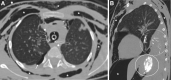

Case summary: A 6-year-old boy presented with ARDS from cement aspiration requiring high-pressure ventilation. He had further complications of tracheal injury with subsequent pneumomediastinum secondary to the alkali burn. He required ECMO to facilitate repeat bronchoscopy for cement particle washout and to enable recovery from ARDS and tracheal injury.